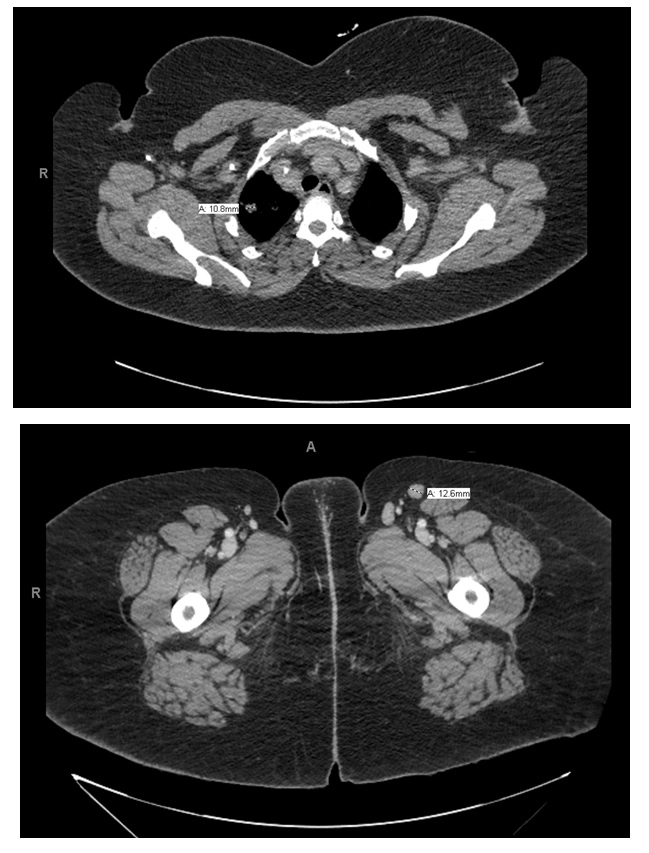

The patient reported a 30 pound weight loss in the last 3 months and recent skin “rash” on back, legs, and arms. CT imaging of the chest and abdomen showed numerous small nodules involving bilateral upper lungs. Cultures of a bronchoalveolar lavage were positive for Pneumocystis jirovecii. Incidentally, bilateral axillary, mesenteric, retroperitoneal, and inguinal lymphadenopathy were also identified on CT (Figure 1).